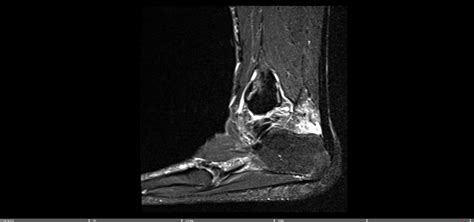

Diagnosing calcification tendonitis involves a combination of physical examination and imaging tests. The diagnostic process typically includes:

• Physical examination: A healthcare provider will assess the range of motion, strength, and tenderness in the affected area.

• Imaging tests: X-rays, ultrasound, or MRI scans can help visualize the calcium deposits and assess the extent of the damage.